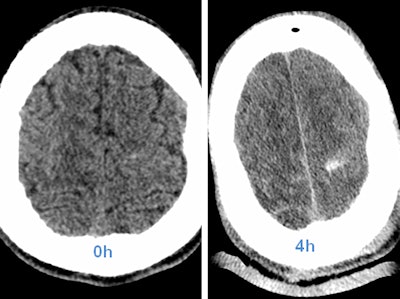

However, very early stages of bleeding, especially in the brain, may be hard to detect, he cautions. Radiologists should be aware of possible hyperacute intracranial bleeding without tremendous density above the surrounding parenchyma.

"If in doubt, repeat the scan. In most cases when a second scan seems appropriate, limiting the procedure to particular organs is sufficient," he said.